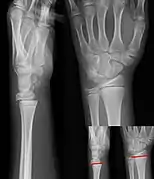

Salter–Harris I fracture of distal radius.

Salter–Harris II fracture of ring finger proximal phalanx.

Salter–Harris III fracture of big toe proximal phalanx.

Salter–Harris IV fracture of big toe proximal phalanx.